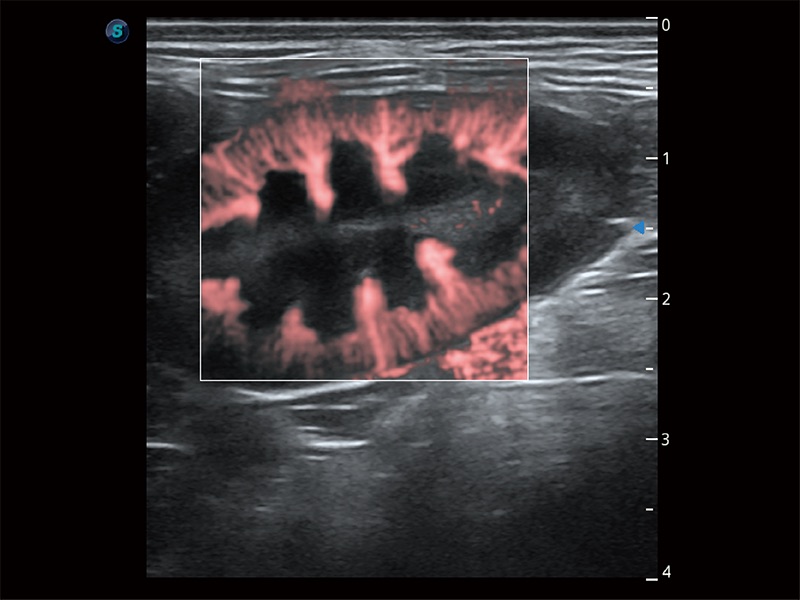

(犬)胎儿主动脉弓立体血流

(犬)肾脏显微血流